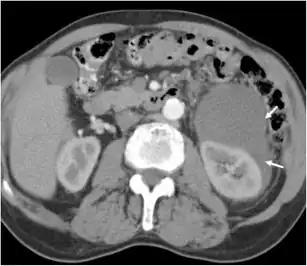

| A homogenous low-density myxosarcoma arrows in the left perirenal space | |